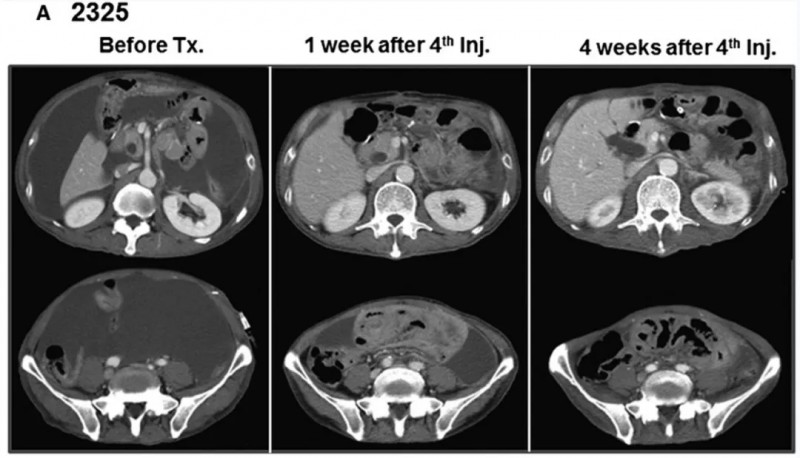

另一例患者2325,治疗前的血性腹水转为清亮(详见下图C),CT示腹水明显减少(详见下图A)。

▲图源“WILEY Online Library”,版权归原作者所有,如无意中侵犯了知识产权,请联系我们删除